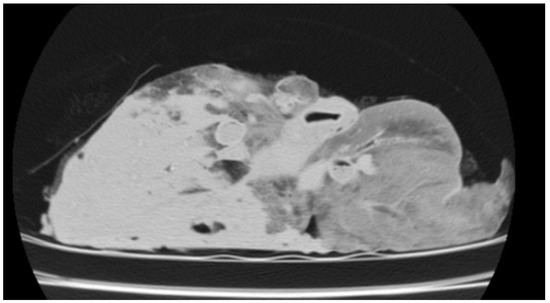

Use of Computed Tomography in the Clinical Diagnosis of Lower Respiratory Tract Diseases in Sheep

Lower airway diseases are a major health concern in sheep, often presenting with overlapping clinical signs that hinder accurate diagnosis. This study evaluated the diagnostic value of computed tomography (CT) in 58 adult sheep examined in northeastern Spain between 2017 and 2024. All animals underwent full clinical examination, CT under general anaesthesia, and post-mortem investigation. CT identified 82 pulmonary lesions, including interstitial pneumonia, respiratory complex, gangrenous pneumonia, caseous lymphadenitis, parasitic pneumonia, pulmonary adenocarcinoma, and pulmonary hydatidosis. Tissue density measurements provided additional information regarding disease stage and severity. The level of agreement between CT findings and definitive diagnoses consistently exceeded that of clinical evaluation, reaching almost perfect concordance for several conditions. Moreover, CT revealed concomitant respiratory pathologies within the same animal, many of which were not detected by conventional diagnostic methods. Although thorough individual clinical examination remains essential for the correct interpretation of imaging findings and the accurate diagnosis of respiratory disorders in the field, these results demonstrate that CT provides superior diagnostic accuracy compared with standard approaches and yields valuable insights for both clinical practice and research. Despite its practical limitations, CT could represent a major advance in improving health, welfare, and productivity in sheep farming. Full article